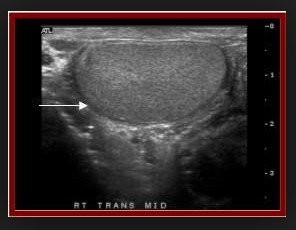

Hasi ultrahang mit mutat ki. Az ultrahang segítségével a belső szervek állapotáról kaphatunk képet. Mit mutat a hasi ultrahang. Szabó andrea radiológus. 50 éves kor fölött mindkét nemnél javasolt rendszeres hasi kismedencei uh és a nyaki erek ultrahang vizsgálata általában akkor írhatnak elő ultrahangos vizsgálatot ha a nyaki területen valamilyen elváltozást sejtburjánzást duzzanatot cisztát vesznek észre vagy ha a nyaki területen nem gyógyuló gyulladás alakul ki.

A hasi ultrahang vizsgálat a májban felfedhet bizonyos jóindulatú változásokat és daganatokat is amelyek kiindulhatnak elsődlegesen a májból de gyakrabban a szervezet más helyén kialakult elváltozások áttétei. Segítségével pontosan meg tudjuk határozni a pajzsmirigy méretét alakját és szerkezetét. Mit mutat a hasi ultrahang. Mit mutat az ultrahang.

észlelhetők az esetleges göbös elváltozások ciszták gyulladásos folyamatok is. Az ultrahang kiváló eszköz arra hogy a pajzsmirigy legkisebb változásait is lekövessük. A hasi ultrahang vizsgálat során a hasüregi és kismedencei szerveket vizsgáljuk. Az epeút rendszer az epevezetékben és epehólyag is remekül áttekinthető így fény derülhet esetleges daganatra illetve az epehólyagban találhat kőre.

Pajzsmirigy ultrahang mit mutat ki hogyan zajlik a pajzsmirigy ultrahangos vizsgálata. Az epehólyag a vese és a hasnyálmirigy panaszok kivizsgálásához is rendkívül hatékony eszköz gyors és fájdalommentes a diagnózis felállítása. Ultrahang vizsgálat bármely életkorban végezhető. Erek doppler ultrahang vizsgálatát dohányzás magas vérnyomás magas koleszterinszint cukorbetegség érelmeszesedés stb.

Az ultrahangkészülék magas frekvenciájú az emberi fül számára nem érzékelhető hanghullámokat bocsát ki melyeket a vizsgáló fej segítségével továbbíthatunk a testszövetek felé.